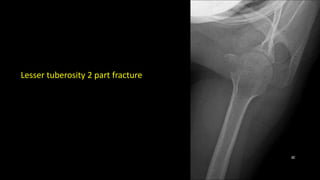

Lesser tuberosity 2 part fracture

Lesser tuberosity 2part fracture